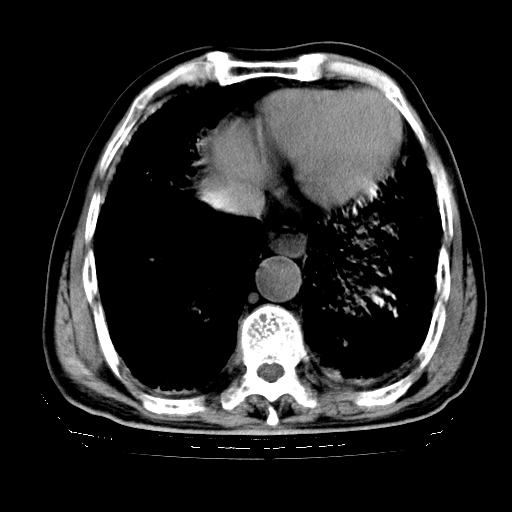

标题: CT25149:男,69岁,反复咳嗽、咳痰五年余,呼吸困难三天。 [打印本页]

男,69岁,反复咳嗽、咳痰五年余,呼吸困难三天。

慢支伴感染、肺气肿、肺心病

慢支伴感染、肺气肿、肺心病。双肺间质性改变(间质纤维化)。